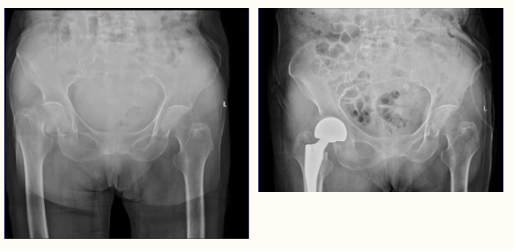

近日,隨州市中心醫(yī)院龍門院區(qū)創(chuàng)傷外科成功為一例高齡老人實(shí)施股骨頸關(guān)節(jié)置換術(shù),手術(shù)順利完成,患者現(xiàn)已下地走路,恢復(fù)良好。像這類年齡大、風(fēng)險(xiǎn)高的手術(shù)已經(jīng)是創(chuàng)傷外科的常態(tài)化手術(shù)。 目前老太太身體狀況恢復(fù) ...